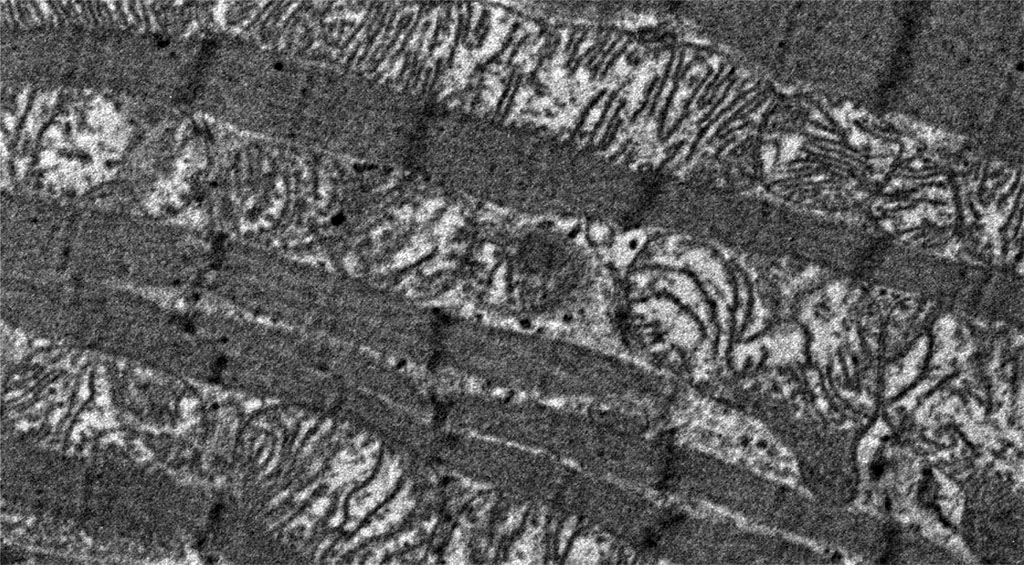

Very noticeable ultrastructural changes were found in the contractile apparatus of contractile cardiomyocytes. In animals of the experimental group, thinning of myofibrils was noted, compared with animals in the control group. The characteristic feature was the presence of areas of overcontraction of myofibrils, characterized by a decrease in the size of sarcomeres (a decrease in the distance between telophragms), a decrease in the size of light discs and the H-zone around the mesophragm (Figure 2 and Figure 3).

Figure 3. Histopathological changes in myofibrils of contractile cardiomyocytes: overt primary hypothyroidism on day 29 from the start of the experiment. Magnification 4200. TEM.

In some areas of contractile cardiomyocytes, the overcontractions of myofibrils were so pronounced that they led to the formation of areas of pronounced overcontraction or contractures (Figure 4), while these changes were absent in the control group. The visually recorded thinning of myofibrils in hypothyroidism may be due to a decrease in the formation of myosin protein in contractile cardiomyocytes, as reported in the molecular genetic study by N. Yousefzadeh et al, where the researchers reported a decrease in the expression of the myosin protein isoform characteristic of adults (heavy chain isoform alpha-myosin), in the myocardium of rats under conditions of hypothyroidism. A decrease in the expression of the adult myosin isoform was accompanied by a compensatory increase in the expression of the fetal myosin isoform (beta-myosin heavy chain isoform) and weakening of the contractile function of the heart, in particular, a decrease in the frequency and strength of heart contractions [27, 28]. Similar changes in the qualitative and quantitative composition of myosin protein isoforms and impaired contractile function were also noted in striated skeletal muscle tissue [29]. Hypothetically, it can be assumed that the change in the expression of the myosin protein is associated with the ultrastructural anomalies of the myofibrillar apparatus that we discovered. Contracture disorders of myofibrils, at the time of their formation, can be clinically manifested by cardiac arrhythmias, and subsequently lead to the loss of the ability to contract this area of the cardiomyocyte, which can lead to both a decrease in heart rate and a decrease in cardiac output. At the same time, hypothyroidism is indeed clinically manifested by similar myocardial symptoms [27]. Thus, the histopathological changes we found in the structure of the contractile apparatus are characteristic clinical signs of this endocrine nosology [30, 31].